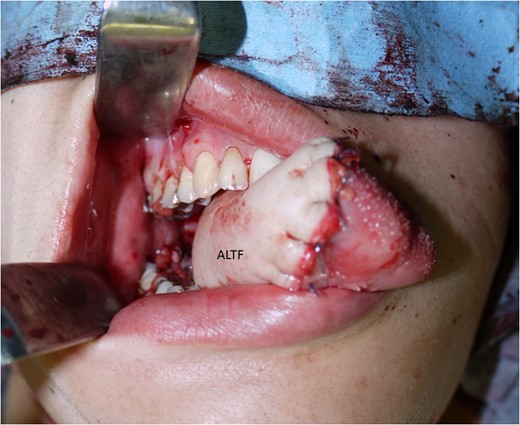

The antero-lateral thigh flap (ALTF) was pulled through, trimmed and sutured to fill the tongue defect.